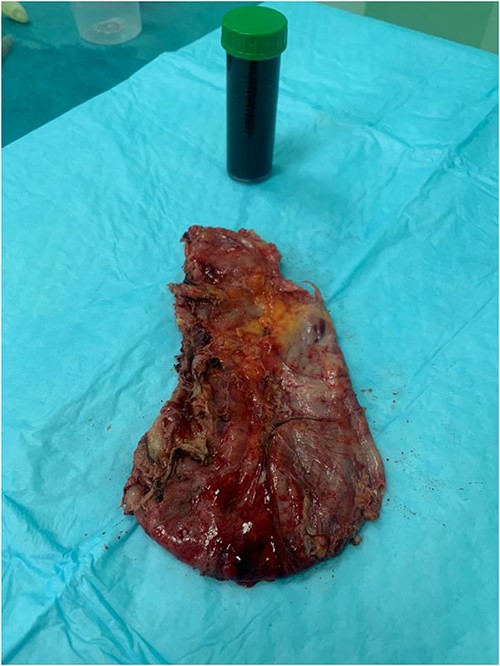

Preoperative prophylactic antibiotics and anticoagulant were given upon induction of anesthesia. The abdomen was accessed safely using a 5-mm vesiport under the guidance of the camera to the left and above the umbilicus. The remaining ports, a 15-mm port 5 cm at the right and above the umbilicus, a 5-mm ports at the left upper quadrant and 5-mm ports at the right upper quadrant were placed with no issues. The cyst was located at the lower pole of the spleen (Fig. 3). The operation consisted of opening the cyst and aspirating dark fluid, removal of the cyst wall (Fig. 4), cauterizing the part of the cyst adherent to the spleen, packing the surgical area with the omentum and removal of the specimen (Fig. 5). The postoperative period was uneventful. The final pathology showed a cyst wall lacking epithelial lining confirming the diagnosis of a pseudocyst, and the cystic fluid showed no malignant cells.